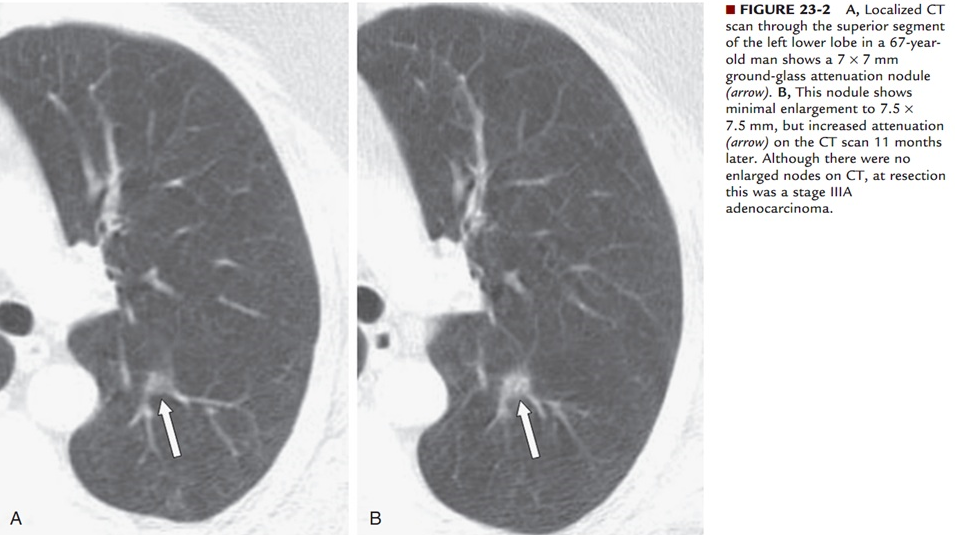

肺小结节的定义及分类。肺小结节指直径≤1cm肺内结节。肺小结节多数为良性病变,如肺部炎症、结核、曲霉菌病、硬化性肺血管瘤、出血、肺间质纤维化等;但也有一小部分肺小结节为恶性病变,如早期肺癌或肺内转移癌。根据肺小结节内部的密度不同,可将其分为纯磨玻璃结节、半实性结节和实性结节,这三类结节为恶性肿瘤的概率分别为18%、63%、7%。磨玻璃结节可以为普通炎症、真菌感染、肺间质纤维化、不典型腺瘤样增生、原位腺癌、微浸润癌、浸润性癌;混合性磨玻璃结节癌变的几率最高,必须引起重视,特别是实性成分大于50%的结节,肺癌的可能性极大。实性结节虽然恶性概率最小,但恶性程度高、进展快。

综上所述,目前最高大上的肿瘤全身PET-CT检查也不能确诊肺微/小结节的良恶性。PET-CT检查最适用于那些直径>8-10mm,且具有中度恶性肿瘤概率的实性或半实性肺结节的评估,以及对肺部结节的术前分期。对于<8mm的肺小/微结节,PET-CT检查诊断价值不高,不常规推荐行PET-CT检查。那么对于<8mm肺微小结节怎么来确诊其良恶性呢?我们可以通过肺螺旋CT薄层扫描、三位重建的结节分析,根据其结节大小、形状、密度(以貌取人,兼顾内涵),以及是否有恶性结节所具有的分叶征、毛刺征、空泡征、支气管充气征、血管征、胸膜凹陷征等来判断其良恶性,更重要的是结合动态随访观察,方能判断其结节良恶性。